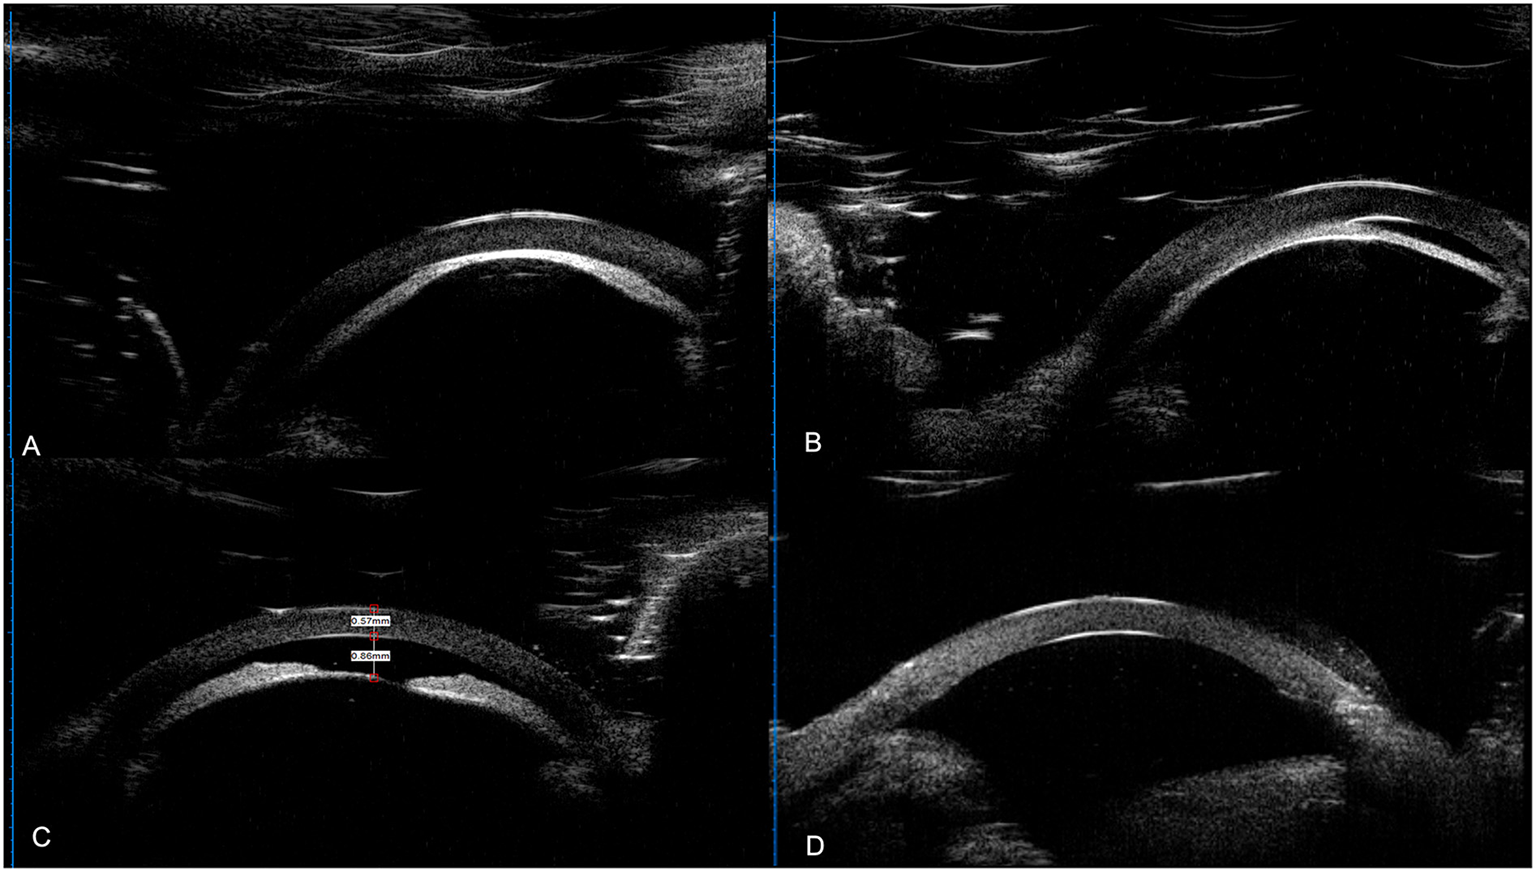

Figure 3

UBM results of the patients. (A) UBM result of left eye of case 3 (a 3-month-old female's); (B) UBM result of right eye of case 8 (a 5-month-old male). A&B: anterior lens displacement, iridocapsular adhesions, capsule-endothelial adhesion, corneal thickening and edema, and obliterated anterior chamber. (C,D) UBM result the right eye of case 15 (a 4-month-old male). (C) Preoperative UBM images showed shallowing of the AC with a depth of 0.86 mm, and anterior lens displacement. (D) 7 months postoperatively, the AC was reconstructed with a depth of 3.2 mm with AC angle open in this aphakic eye.